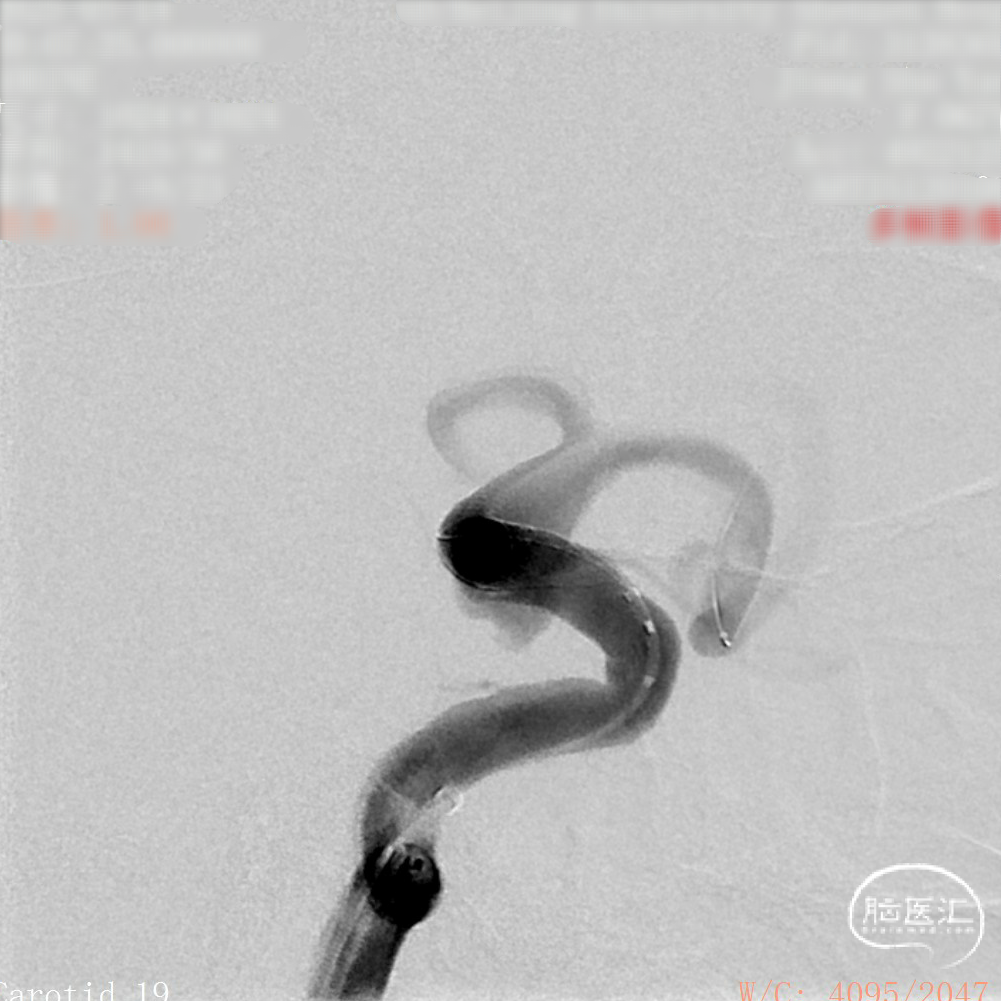

DSA造影:

工作角度:

微导管到位后释放支架头端。

头端完全打开,锚定。